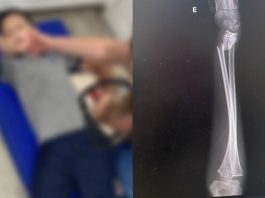

Dois jovens ficam feridos após carro bater contra poste em Joinville

Duas vítimas estavam sem cinto de segurança